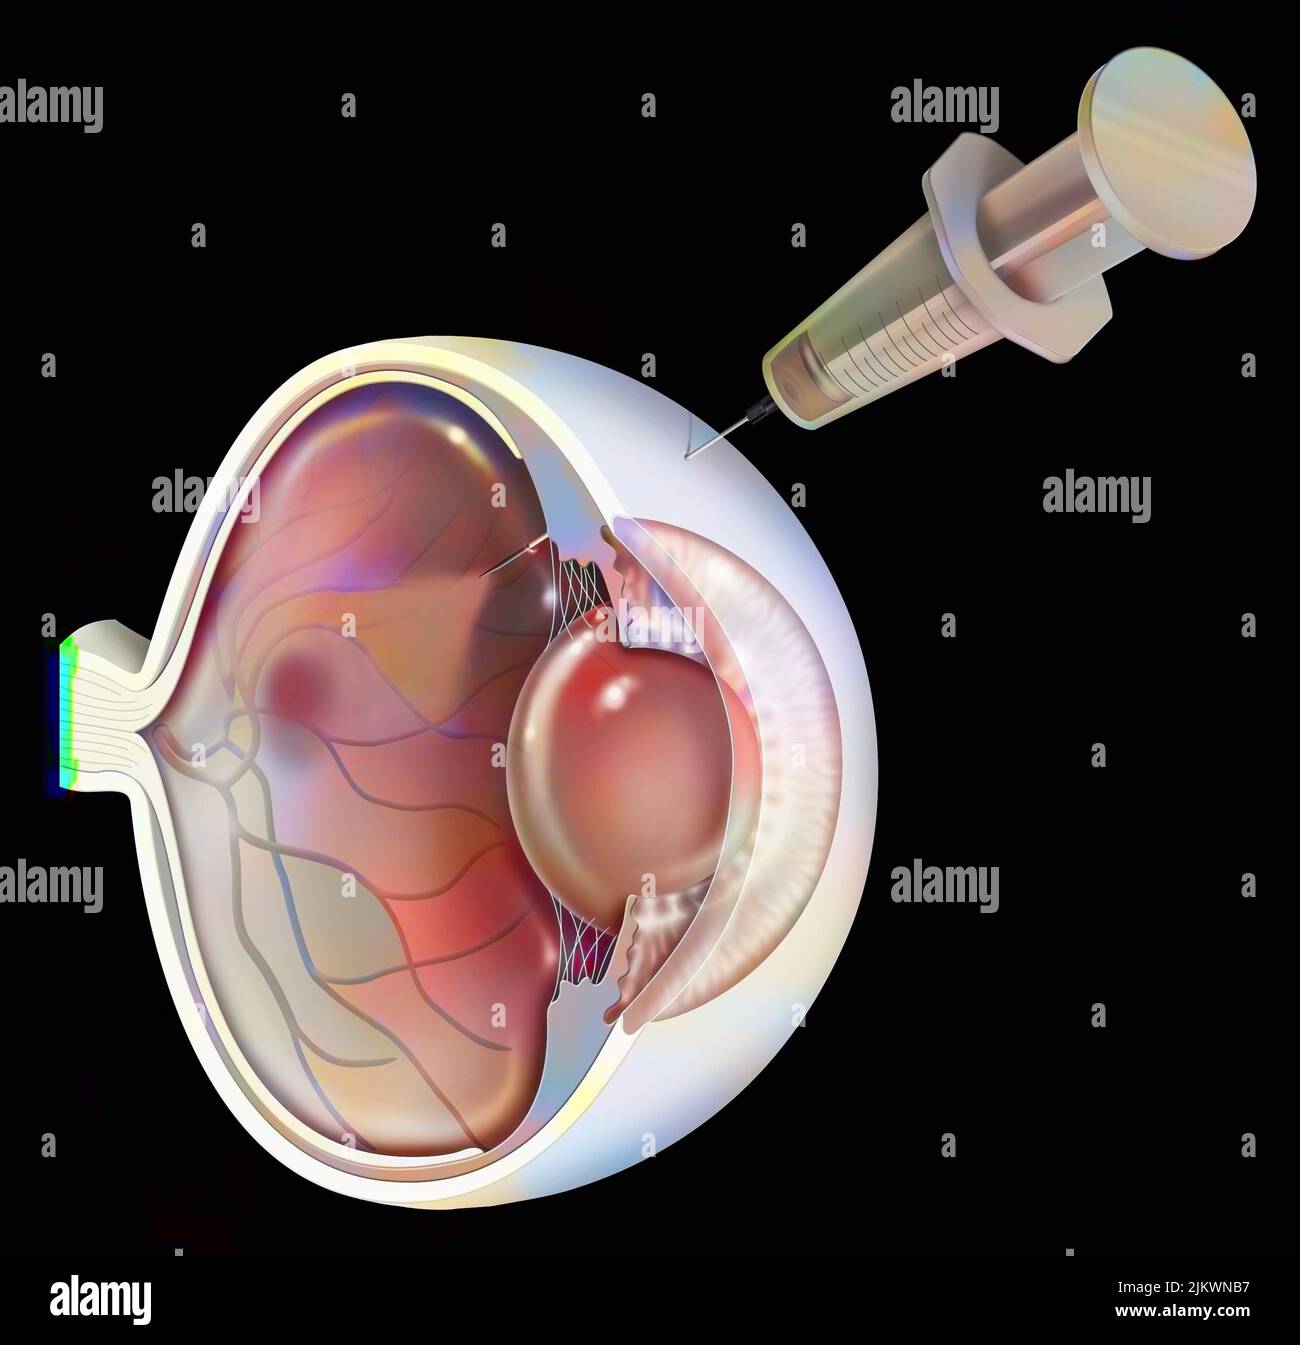

RF2JKWT9A–Oeil, cataracte, phacoémulsification - étape 2: Consiste à casser la lentille avec une sonde.